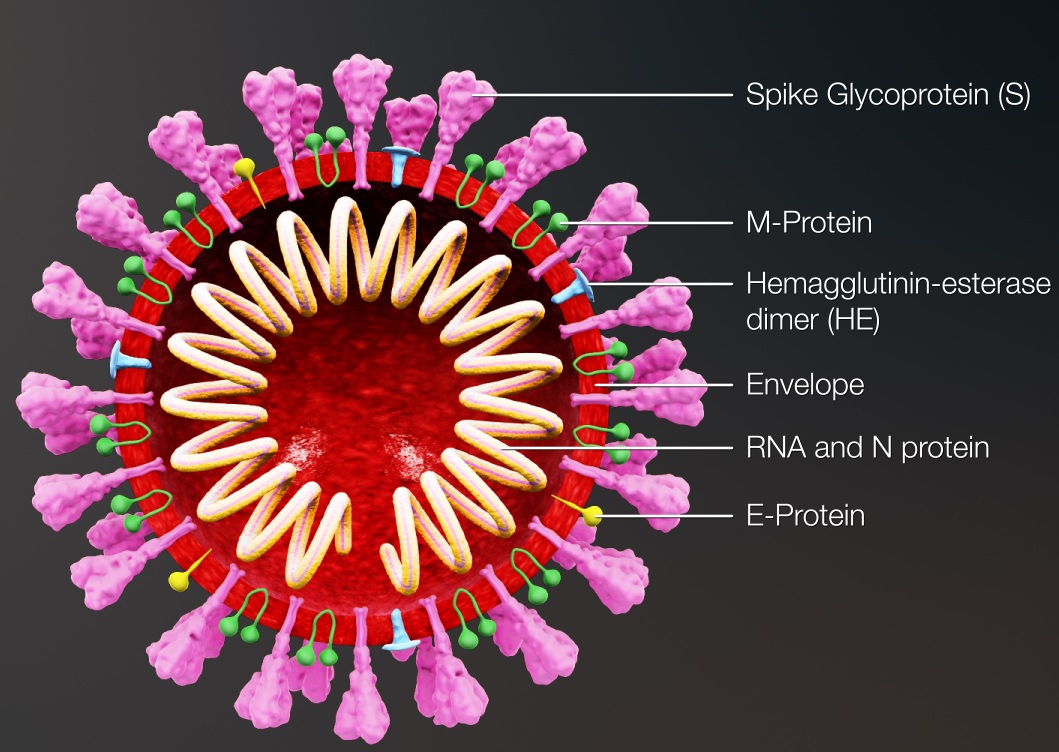

کروناویروسها دارای بزرگترین ژنوم در میان تمام ویروسهای RNA دار انسانی (27 تا 32 کیلوباز) میباشند. ژنوم SARS-CoV-2 پروتئینهای ساختمانی شامل چهار پروتئین مهم S ،E ،M ،N و مجموعهای از پروتئینهای فرعی را کد میکند.

قسمت 27: زیستشناسی مولکولی کووید-۱۹

کروناویروس دارای یک RNA ژنومی شامل 29891 نوکلئوتید بوده که پروتئینهای (S (Spike) ،E (Envelop ، (M (Membrane و (N (Nucleocapsid را کد مینماید. این چهار پروتئین، پروتئینهای ساختاری بوده و برای ساختن ذرات ویروسی مورد نیاز هستند.

قسمت 13: ساختار کلی کرونا ویروس جدید و گیرندههای آن

ساختار کرونا ویروس جدید CoV2-SARS حاوی RNA تک رشته با قطبیت مثبت (sense Positive ) و احاطه شده توسط یک غشای دو لایهی لیپیدی است. هر ذرهی این ویروس تقریباً 50 -200 نانومتر قطر دارد. اسکلت این ویروس دارای چهار پروتئین ساختاری به نامهای S ،N ،E و M میباشند که مهمترین آنها، پروتئین (Spike (S میباشد. پروتئین N ،در ساختار ژنوم ویروس قرار دارد و سه پروتئین دیگر به نامهای پروتئینهای S ،E و M با یکدیگر پوشش ویروس را ایجاد میکنند.